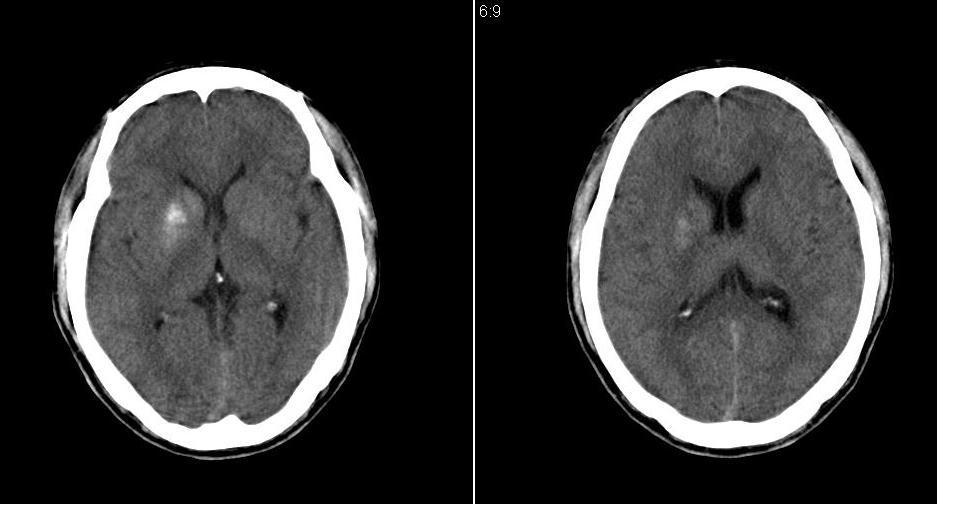

以下是引用tianhep在2007-5-9 19:53:00的发言:[br]这个部位多为苍白球钙化,苍白球钙化往往双侧对称。有外伤史而无症状。首先考虑为苍白球钙化。短期内复查一次就可。

以下是引用狙击手在2007-5-9 19:52:00的发言:[br]病灶边界模糊,外周无水肿带,无占位效应,无任何不适,考虑钙化。

以下是引用gyh6308在2007-5-9 21:10:00的发言:[br]这种病例我见过,是脑血管畸形所致的钙化,做cta可观察